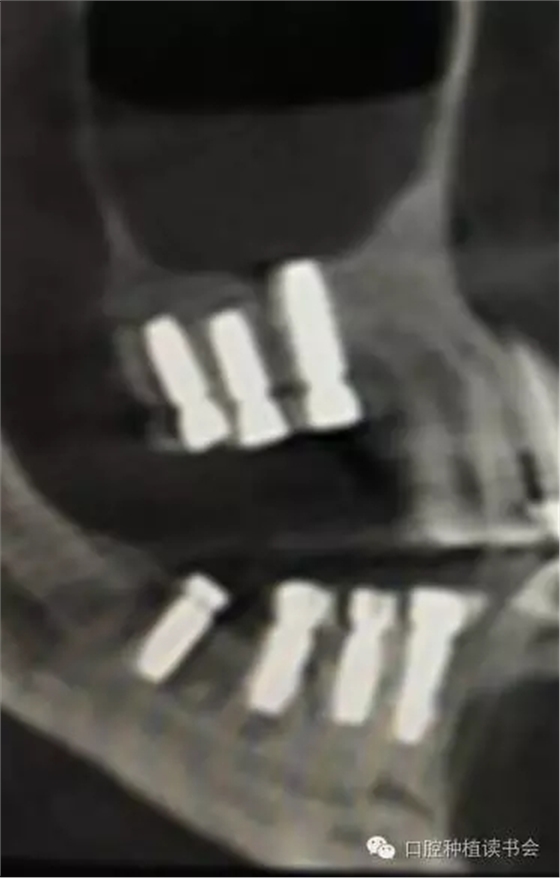

除了諸多解剖因素和生理病理因素,是否選擇上頜竇提升術(shù)(尤其是側(cè)壁開(kāi)窗術(shù))或判斷術(shù)后預(yù)期,與病人是否有基礎(chǔ)病(如糖尿病)、病人是否經(jīng)過(guò)頭部放療、是否因骨質(zhì)疏松而長(zhǎng)期服用雙膦酸鹽類藥物等相關(guān)因素均緊密相關(guān)。根據(jù)上頜竇的解剖特點(diǎn),在長(zhǎng)期實(shí)踐中,基本形成了2類上頜竇底提升的方法。1、經(jīng)牙槽脊頂提升粘膜的方法稱為內(nèi)提升,具有代表性的技術(shù)是1986年Tatum提出的經(jīng)牙槽脊提升上頜竇技術(shù)和1994年Summers提出利用內(nèi)提升器械自牙槽嵴頂入路的沖頂式上頜竇內(nèi)提升技術(shù)(osteotome sinus floor elevation,OSFE),又稱閉合式提升術(shù) (closed sinus lift technique)。前者通過(guò)牙槽脊頂切口,用特殊的窩洞成型器代替擴(kuò)孔鉆,敲擊使上頜竇底“骨折”,從而完成提升術(shù)。后者是在竇底1-2mm處用提升器進(jìn)行敲擊抬高竇底。其后多年來(lái)人們利用工具的改革創(chuàng)新,使內(nèi)提升技術(shù)有了很大的變革和進(jìn)步,如利用超聲骨刀或其他專用器械去除竇底骨質(zhì),利用球囊等工具以水、氣壓抬高上頜竇粘膜;利用環(huán)鉆進(jìn)行上頜竇底內(nèi)嵌骨塊內(nèi)提升;也有通過(guò)磁力車針進(jìn)行上頜竇底骨質(zhì)預(yù)備,通過(guò)同極排斥的原理,當(dāng)竇底骨質(zhì)去盡后,粘膜被車針“彈升”;也有通過(guò)牙槽脊頂開(kāi)窗植骨的病例報(bào)道(Winter,2003)。因此,隨著上頜竇提升技術(shù)的不斷改進(jìn)、各種新型手術(shù)器械的出現(xiàn),在RBH<4mm的情況下,上頜竇內(nèi)提升的方式也越來(lái)越被大家所采用(Nedir,2009)。2、經(jīng)側(cè)壁開(kāi)窗分離粘膜抬高竇底的方法稱為外提升(Lateral Window Technique)。早期由Philip?Boyne提出,后來(lái)上頜竇側(cè)壁開(kāi)窗在粘膜和竇底之間進(jìn)行骨增量的術(shù)式逐步應(yīng)用開(kāi)來(lái)。側(cè)壁開(kāi)窗后是否同期植入種植體,根據(jù)RBH,種植體穩(wěn)定性的預(yù)判而決定。總的來(lái)說(shuō),上頜竇外提升術(shù)的成功率86%~100%(Jensen,2009)。根據(jù)CBCT圖像,不但可以提供術(shù)前的種植計(jì)劃指導(dǎo),而且上頜竇外提升術(shù)后的效果,尤其是檢查種植體腭側(cè)是否有植骨不全,都會(huì)一目了然。(圖10-12)